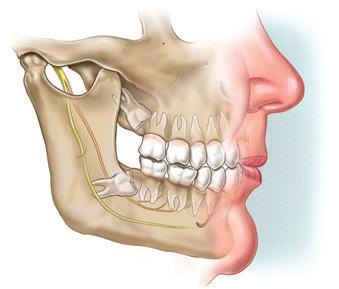

Orthognathic surgery, a discipline dating back to the 1840s, addresses maxillomandibular disharmonies and enhances both aesthetic appearance and function.1 This surgical field has had substantial advancements from its inception, particularly following the contributions of Hugo Obwegeser, who introduced techniques such as the bilateral sagittal split and Le Fort I osteotomy, which remain integral to contemporary orthognathic surgery.2 In recent years, advancements in the accuracy of computed tomography (CT) and cone beam computed tomography (CBCT) have spurred a shift towards three-dimensional (3D) virtual surgical planning (VSP).3 The widespread use of VSP has led to evidence supporting its accuracy in orthognathic surgery planning and execution.4

The adoption of VSP has revealed a plethora of advantages. Notably, Swennen and colleagues underscored the potential of VSP planning in assessing treatment outcomes through voxel-based rigid registration and superimposition techniques.3 Additionally, VSP serves as a communication tool among specialists, technicians and patients, with applications in education.3 VSP offers benefits such as enhanced accuracy in condylar positioning through splint construction using computer-aided design and computer-aided manufacturing (CAD and CAM), improved diagnosis and quantification of facial asymmetry, and potentially increased cost-effectiveness.5

In all cases that involved the maxilla, a Le Fort I osteotomy was conducted. In cases that involved the mandible, a bilateral sagittal split osteotomy was performed. Standard fixation miniplates and screws were used in all cases. If both mandible and maxilla movements were required, then the Le Fort I osteotomy was completed and fixated with miniplates before the mandibular movements.